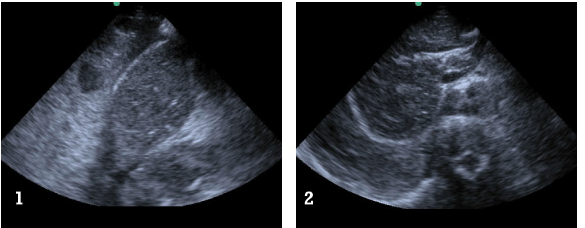

The RUQ FAST scan:

Seek and ye shall find 3

FAST ultrasound evaluation was performed after the patient was log-rolled in both directions – first to the left and then to the right.  Subsequently the patient was taken to CT scan. He remained hemodynamically stable. Below the comparative findings of FAST vs CT scans.

IMAGING

FAST ULTRASOUND

CT

RUQ

perihepatic free fluid

SUBXIPHOID

no pericardial effusion

LUQ

no free fluid

trace perisplenic free fluid

PELVIC

Given stab wound to left anterior chest with presence of free fluid in the abdomen (with hepatic and splenic injuries identified on CT), patient was taken to the operating room. Injury to pericardium itself without pericardial effusion was suspected on CT. During the surgical exploration it appeared that the stab wound to the left chest only nicked the pericardium (no blood within pericardial sac), while penetrating the left diaphragm, left lobe of the liver, stomach, spleen and pancreatic body.